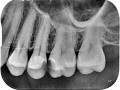

Rozległa torbiel zawiązkowa żuchwy

Paulina Adamska, Maria Mikołajska, Anna Janowska, Anna Starzyńska